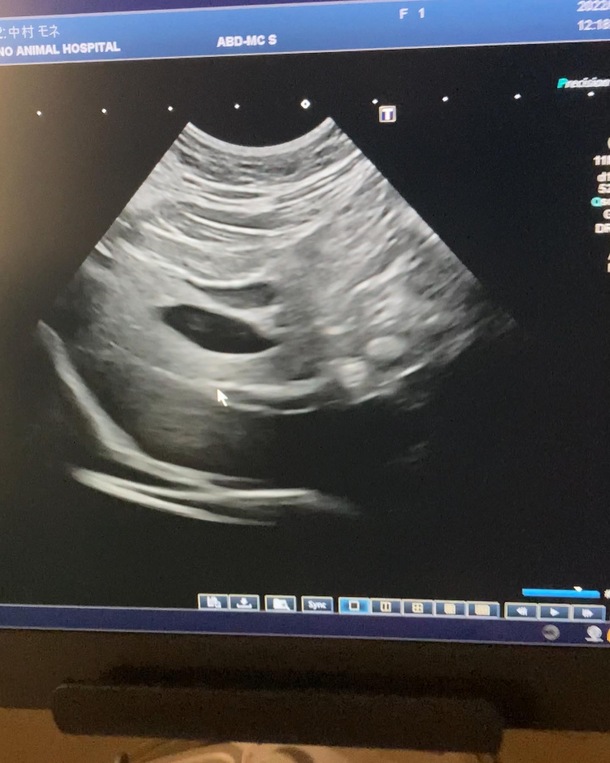

定期検査のご報告

術後の定期検査に行ってきました。

結論から言うと胆嚢付近に小さな嚢胞はありましたが、現状問題ではないそうです。

※前回の病理検査で良性は確定したので、嚢胞が肥大しなければ大丈夫とのこと🌼

次、1ヶ月後の9月に再度検査して、大きくなってたり体調変化があればCT検査の流れになります。😭